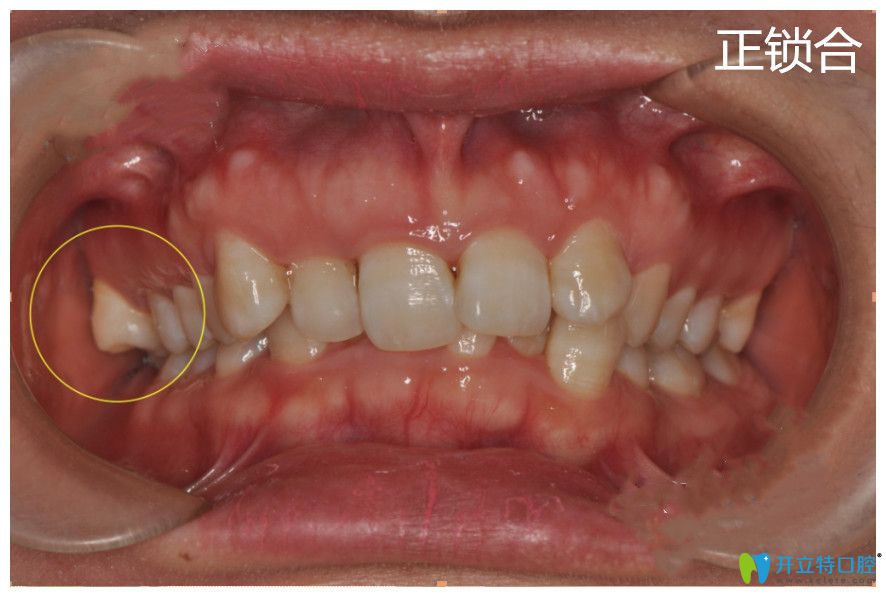

淺談鎖合牙的治療方法及牙齒鎖合矯正步驟

輕微的鎖合牙沒有明顯的癥狀,也不會表現(xiàn)出來。一旦出現(xiàn)牙齒嚴(yán)重鎖合就很難解決了,這會影響咀嚼功能,從而造成偏側(cè)咀嚼,甚會導(dǎo)致面部兩邊不對稱。一起來看鎖合牙的治療方法及步驟